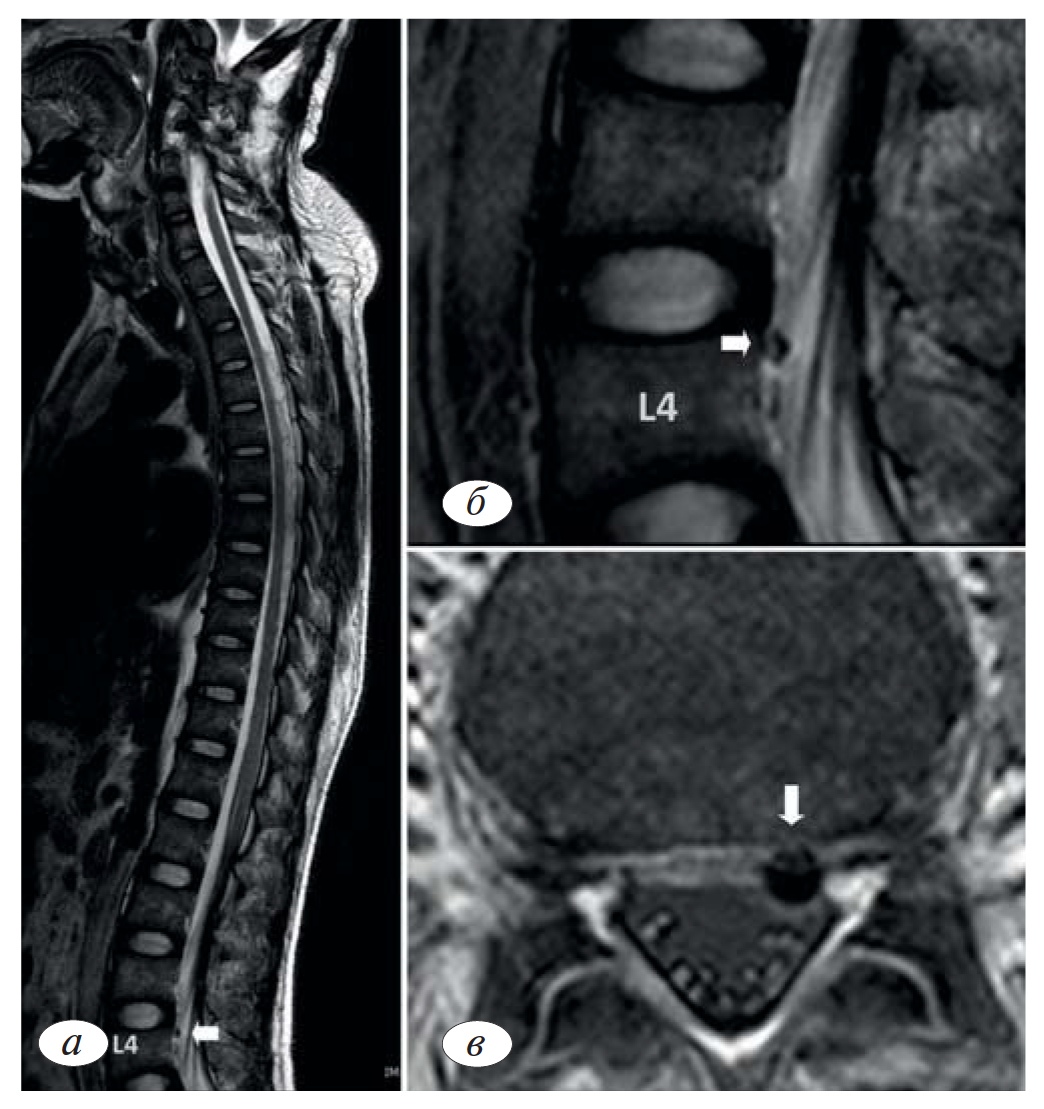

Авторами отмечается, что выраженного улучшения неврологических функций выявлено не было. Тем не менее на картине МРТ определялось накопление трансплантированных стволовых клеток в субарахноидальном пространстве поясничного отдела спинного мозга и области конского хвоста (cauda equina) (рис. 17).

По данным МРТ, клетки были обнаружены в области нижних (каудальных) отделов позвоночника и спинного мозга, что может быть связано с действием гравитации. Этим в свою очередь можно объяснить отсутствие улучшения состояния пациента в период после оперативного вмешательства, поскольку клетки не проникли к месту повреждения (в рассматриваемом клиническом примере оно находилось в верхних шейных сегментах спинного мозга). Кроме того, значительное время, прошедшее после травмы (4 года), является фактором, значительно снижающим прогноз всех видов терапии в отношении неврологического (двигательного, чувствительного) статуса.

Рис. 17. Изображение МРТ пациента с повреждением спинного мозга (33 года) в области шейного отдела позвоночника, полученное через 1 сут после введения меченных магнитными наночастицами клеток путем люмбальной пункции.Сагиттальные Т2-взвешенные изображения позвоночника в целом (а) и фрагмента поясничного отдела (б); в — аксиальное изображение позвонка LIV. Белыми стрелками на всех изображениях отмечено накопление меченных магнитными наночастицами клеток. В шейном отделе спинного мозга клетки обнаружены не были (по A. Chotivichit и соавт. [33]).

Fig. 17. MRI image of a patient with spinal cord injury (33 years) in the cervical spine, obtained 1 day after the introduction of magnetic nanoparticle-labeled cells by lumbar puncture. Sagittal T2-weighted images of the spine as a whole (a) and a fragment of the lumbar spine (b); C — axial image of the vertebra LIV. White arrows on all images indicate the accumulation of magnetic nanoparticle-labeled cells. In the cervical spinal cord cells were not found (for A. Chotivichit et al. [33]).